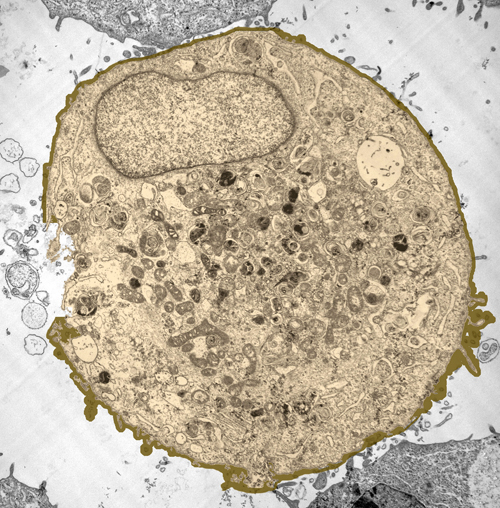

Si daca nu ar fi decat o iluzie? Daca ideea de a ataca cancerul in mecanismele genetice care il genereaza nu ar fi decat un vis? Pe masura ce se acumuleaza informatiile cu privire la infinitele evenimente moleculare care anima o celula canceroasa, si care sfarsesc in arhivele industriei farmaceutice, doldora de compusi „miraculosi” care nu au schimbat nimic, un sens de neputinta ii „sugruma” pe cercetatorii implicati zi de zi in lupta din „transee”.

In fapt, introducerea in clinici a noilor terapii a aratat ca selectivitatea lor extrem de ridicata se poate transforma intr-un bumerang, avand in vedere ca nu exista un bolnav de cancer identic cu altul, si ceea ce merge la pacientul A si la genele lui nu neaparat va functiona si la pacientul B, chiar daca, aparent, cei doi sufera de aceeasi boala. Cu alte cuvinte, medicamente care au costat ani de munca si investitii cu sase zerouri risca sa devina produse de nisa, bune doar pentru un mic procent de persoane care raspund unui anumit profil genetic.